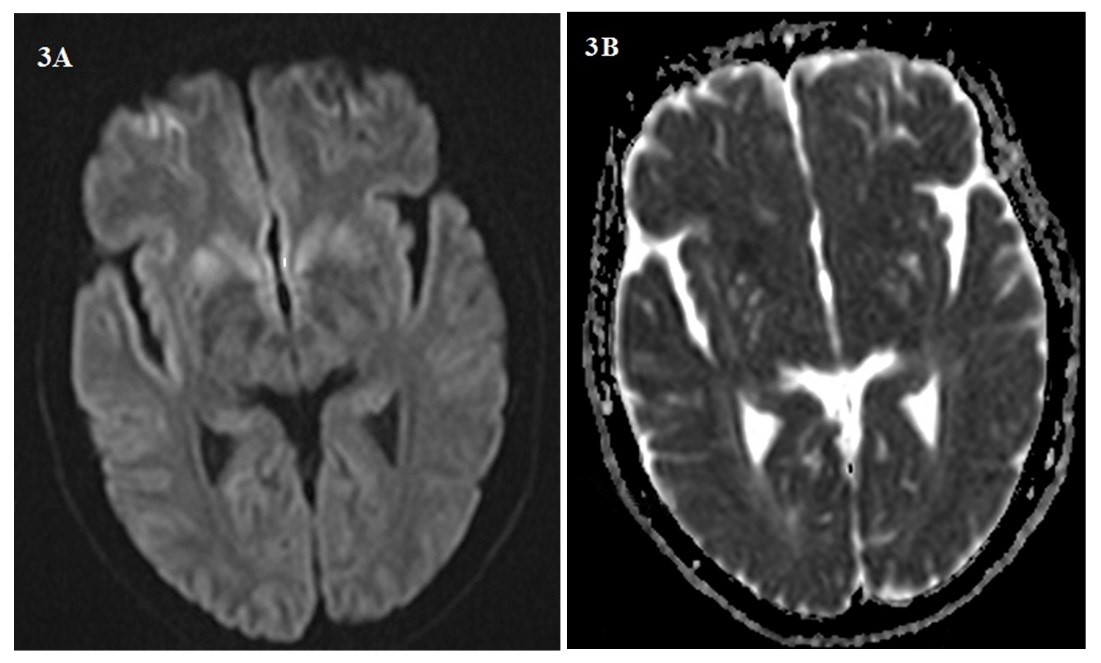

Background: Creutzfeldt-Jakob disease (CJD) is a progressive and fatal prion disease in human and its annual incidence is estimated one per million. Sporadic form of CJD is the most common form of the disease that involved 85% of cases. Case Report: We presented two cases of CJD with the different clinical presentation; a 58-year-old woman who referred with amnesia, depression and a 59-year-old woman with ataxia as her chief complaint. Based on the findings and roled-out the other differential diagnosis, the CJD was confirmed. Both of them died before 12 months after diagnosis. Conclusion: Although CJD is a rare disease with different clinical manifestation, it is considered as one the differential diagnosis of progressive dementia.[GMJ.2019;8:e1357]Â